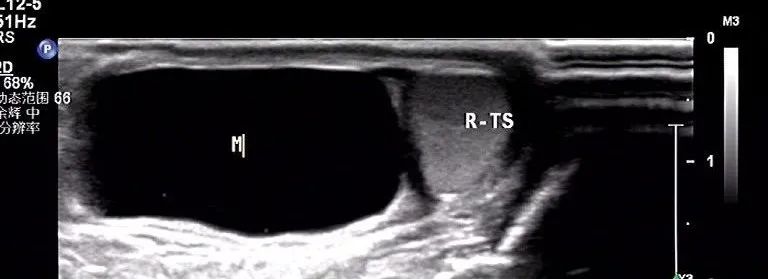

超声表现为:为腹股沟区或阴囊根部无痛性包块,触诊呈囊性感。

精索鞘膜积液:积液位于睾丸上方,呈规则的囊状无回声区

精索鞘膜

如果积液发生于腹股沟区的精索周围的鞘膜腔内,就形成了精索鞘膜积液,也称精索囊肿(如图4所示)。那么,重点来了,精索鞘膜积液是不是只局限于腹股沟区呢?

图4示意图显示较小时的精索鞘膜积液

答案是否定的。如果精索鞘膜积液量过大,其所形成的囊肿可延伸进入阴囊内,并挤压睾丸,所以尽管超声检查发现阴囊内存在液性暗区,但其实并非睾丸鞘膜积液(如图5所示)。

图5示意图显示积液量较多时的精索鞘膜积液

睾丸鞘膜积液若积液量较大,无法经阴囊扪及睾丸;而精索鞘膜积液凸入阴囊内,由于睾丸受挤压而位于一角,触诊可及。